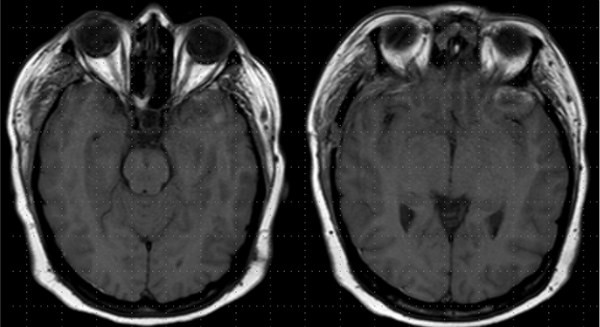

En RM de cerebro se observa lesión espacio ocupante selar-supraselar con aspecto multilobulado que invade cisterna interpeduncular y desplaza estructuras del tercer ventrículo. La misma es hiperintensa espontáneamente en T1 con captación heterogénea de contraste, hiperintensa en T2 (Figura 1). En secuencia de angioresonancia se observa su relación medial respecto a arterias carótidas no comprometiendo las mismas (Figura 2). A partir de éstas imágenes obtenidas en resonador 3 Tesla, en el Departamento de Innovación Tecnológica del Instituto Cardiológico de la Ciudad de Corrientes se realizó un proceso de segmentación de las distintas partes de interés (tumor, arterias, nervios ópticos y globos oculares). Para esto se utilizó el software “Open Source 3D Slicer (versión 4.11)” (Figura 3). Una vez segmentadas las regiones de interés, se realizó, mediante una impresora 3D “MAX” de la empresa Creatbot, un modelo 3D cuyos materiales consistieron en poliácido láctico (PLA) y poliuretano termoplástico (Figuras 4 y 5). Con el mismo, se realizó la planificación del abordaje quirúrgico.

Figura 1: RM en secuencia T1 cortes a) 1axial, se observa lesión espontáneamente hiperintensa y su relación con vasos del polígono de Willis. b) RM en secuencia T1 corte sagital, donde se observa extensión supraselar de la lesión comprimiendo lamina terminalis

Figura 6: RM cortes axiales en T1 evidenciando ausencia de lesión tumoral.